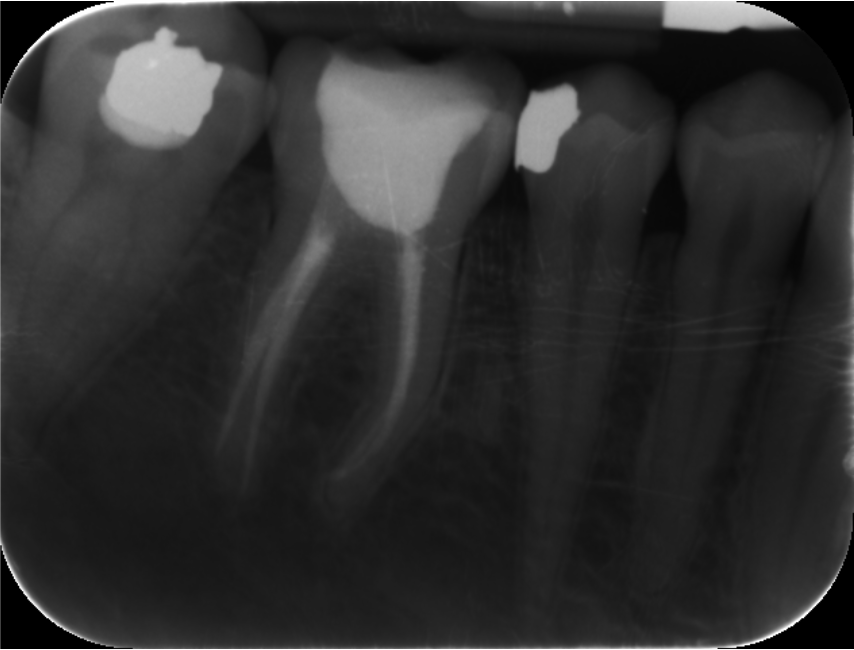

Crowns and onlays by Professor Brian Millar

This course solidified my knowledge and allowed me to practice various cuspal coverage treatments including overlays, onlays and vonlays. I was able to learn about the different preparation techniques and margins required for each indirect material.